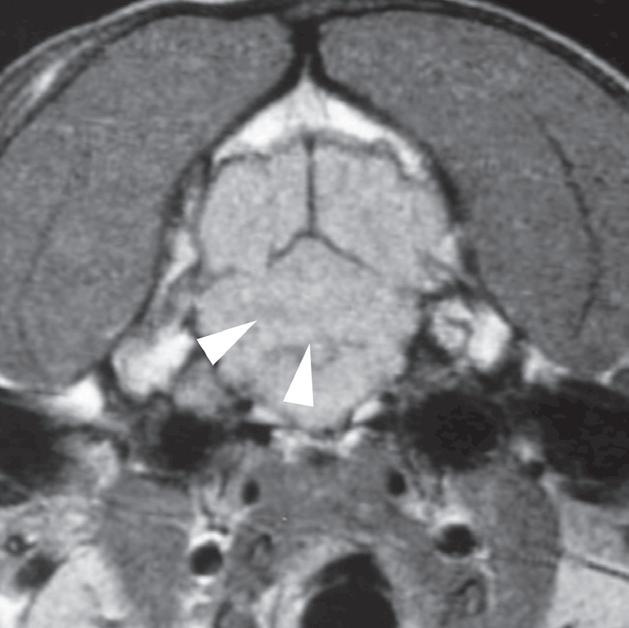

U 6-letniego samca rasy rhodesian ridgeback od 4 dni obserwowano objawy wskazujące na chorobę móżdżku. Stwierdzono słabo odgraniczony, izointensywny w T1 i hiperintensywny w T2 obszar w robaku i lewej półkuli móżdżku (a, b – groty strzałek), któremu nie towarzyszył żaden znaczący efekt masy. Po podaniu kontrastu nie zobrazowano wzmocnienia zmiany. Test immunofluorescencji pośredniej (IFA) wykazał miano zgodne z aktywnym zakażeniem Neospora. Badanie pośmiertne wykonane ok. 3 miesięcy po wstępnym rozpoznaniu potwierdziło martwicze, ziarniniakowe zapalenie móżdżku z pierwotniakami odpowiadającymi Neospora wewnątrz ognisk